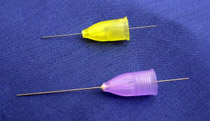

蚊に刺されても痛くないように、針が細ければ細いほど痛みは抑えられます。

当院では現在発売されている中でも最も細い針を使い、ソフトに注射することで痛みを抑えます。